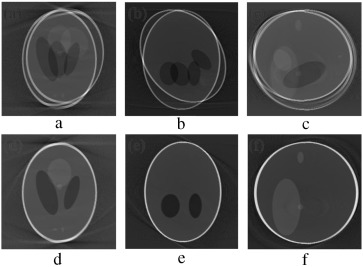

(a–c) Projection at 160°,180° and 200° source position. (d–f) Axial, coronal and ...

Figure 9.

(a–c) Projection at Failed to parse (MathML with SVG or PNG fallback (recommended for modern browsers and accessibility tools): Invalid response ("Math extension cannot connect to Restbase.") from server "https://mathoid.scipedia.com/localhost/v1/":): {\textstyle 160\mbox{°},180\mbox{°}}

and Failed to parse (MathML with SVG or PNG fallback (recommended for modern browsers and accessibility tools): Invalid response ("Math extension cannot connect to Restbase.") from server "https://mathoid.scipedia.com/localhost/v1/":): {\textstyle 200\mbox{°}}

source position. (d–f) Axial, coronal and sagittal slices of the translational and rotational motion corrupted reconstructed volume.